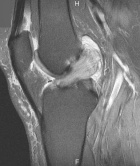

P.P. - 55 year old female c/o right knee pain x 1.5 years. Pain is dull, intermittent, worse with activity. No mechanical symptoms. No history of trauma. Treatment with NSAIDs, aspirations, viscosupplementation, intraarticular steroids provide minimal relief.

Zoom image: Radiological image Radiological image.